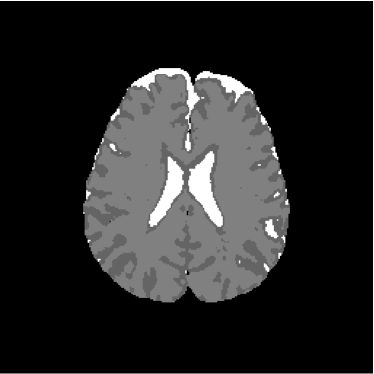

Figure 2: Axial DW-MR image of 13th slice with diffusion exponent of 500 s/mm2

To perform the training we chose 13th slice of each volume sample (figures 1, 2 and 3), once this slice shows the temporal corni of the lateral ventriculi. The exhibition of such structures facilitates the analysis of the specialist and helps him to find a correlation between data generated by our computational tool and a priori specialist knowledge. Furthermore, slice 13 presents a considerable amount of artifacts out of the cranial region.

Figure 13 shows the training set mounted on the 13th slice of the volume of ADC maps. Figures 14 and 15 show the ground truth volume and the 13th slice, respectively.

Figure 14: Ground truth image (13th slice) generated by polynomial net classification

Figure 28 shows 13th slice of classification result obtained by the use of the objective dialectical classifier. Figure 29 exhibits 13th slice of classification result after performing post-labeling, whilst figure 30 shows the entire volume generated by ODC classification.

The training process of ODC algorithm resulted in 6 classes. These classes were reduced to 4 after manual post-labeling, merging 3 classes out of brain region, namely image background, noise and cranial box. The post-labeling is manual because all 3 cited regions are statistically different and, consequently, they are merged due to our interest in classes more related to the brain regions. On figure 29 it is possible to notice that ODC was able to distinguish white matter from the gray matter present in the interface between liquor and white matter.

Figure 29: 13th slice of objective dialectical classification after post-labeling

Figures 33, 34 and 35 show binary images of 13th slice of ODC classification, showing liquor (cerebrospinal fluid, CSF), gray matter (GM) and white matter (WM), respectively, whilst figures 37 and 38 show the respective morphological spectra and accumulated morphological distributions. Both morphological spectra and accumulated morphological distributions were obtained using structure element square 3×3333\times 3 center (2,2)22(2,2).

Figure 34: 13th slice of gray matter volume detected by method ODC

Observing figure 34 indicating the detection of gray matter by the objective dialectical classifier, we can perceive the significative reduction of gray matter in brain frontal lobule, better seen in superior part of image. This lobule is directly related with the reduction of recent memory.